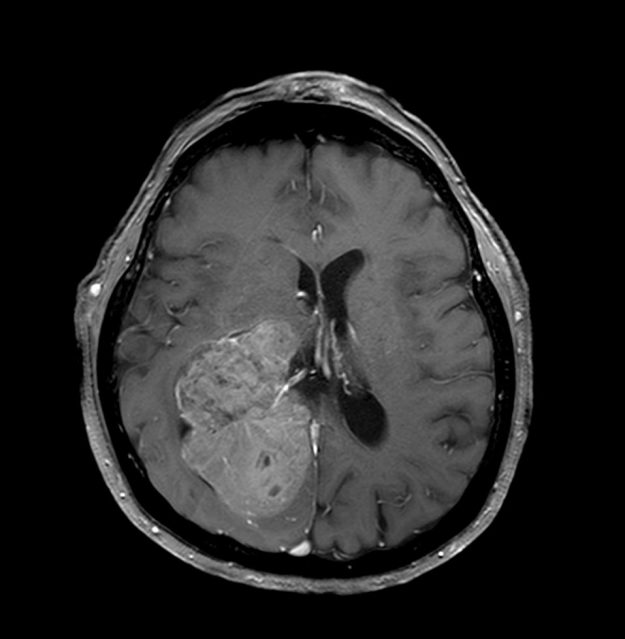

Μηνιγγίωμα περιοχής Επίφυσης

Ασθενής γυναίκα, 52 ετών η οποία παρουσίασε υπακουσία και επεισόδια πάρεσης του προσώπου. Ο απεικονιστικός έλεγχος με μαγνητική τομογραφία ανέδειξε ευμεγέθη όγκο στην περιοχή της επίφυσης (κωνάριο) με πίεση επί του μεσολοβίου, του τετραδύμου πετάλου και λοιπών εν’ τω βάθει δομών. Διενεργήθη δεξιά ινιακή, διασκηνιδιακή, διαδρεπανική προσπέλαση και ολική αφαίρεση της βλάβης. Η μετεγχειρητική αξονική…